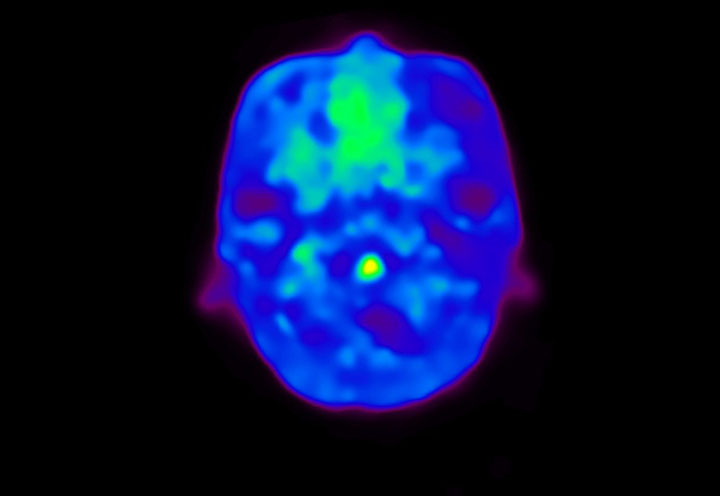

Head / Case4 : Amyloid

Coronal

Courtesy : Kindai University Hospital

- Injected dose: 3.21 MBq/kg, 18F-Flutemetamol

- Uptake time: 100 minutes

- Scan time: 20 minutes